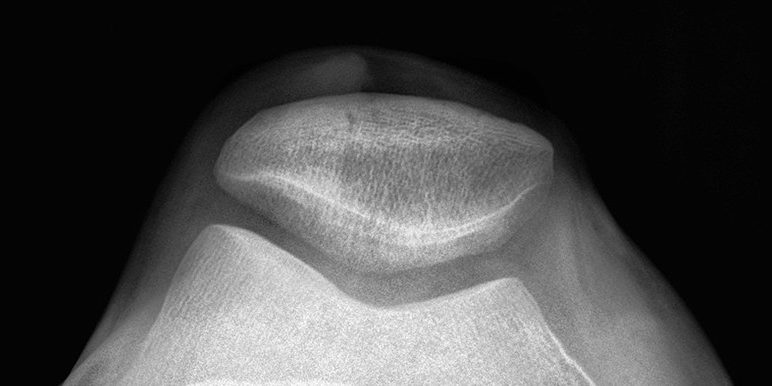

Image by Perfect Zero via Flickr